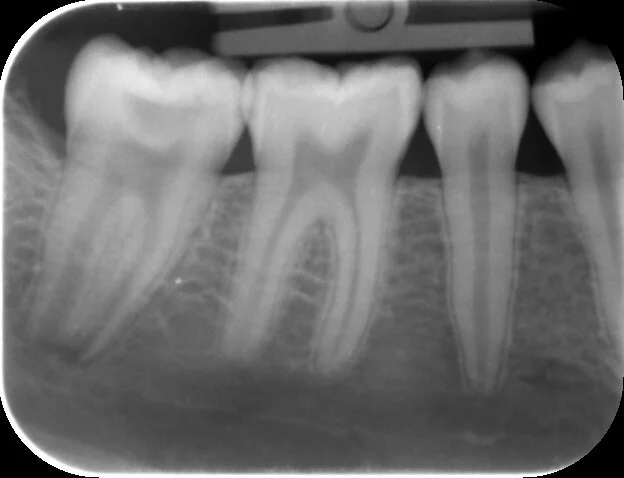

An occlusal carious lesion breaching the pulp horn of the second molar, the apices are not fully developed

Two years and no symptoms later this PA shows continued root development of the second molar